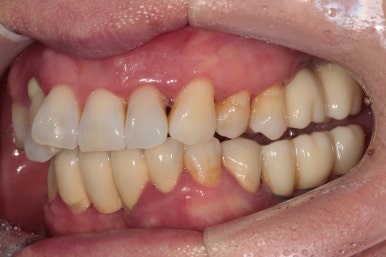

고개를 좌우로 돌려 좌측과 우측을 살펴보았습니다.

제가 앞에서 본다고 생각하시면, 왼쪽 사진이 우측이겠지요?

우측 가쪽 앞니 (측절치)에서 active하게 농양이 나오고 있는 것을 보실 수 있어요.

당연히 위턱 앞니들이 모두 흔들흔들 합니다.

어금니는 임플란트로 치료를 받으셨지만, 앞니는 틀니를 해야한다는 말에 치과 방문을 미루고 미루시다가 소문을 듣고 저희 치과를 방문해주신 경우였어요..!